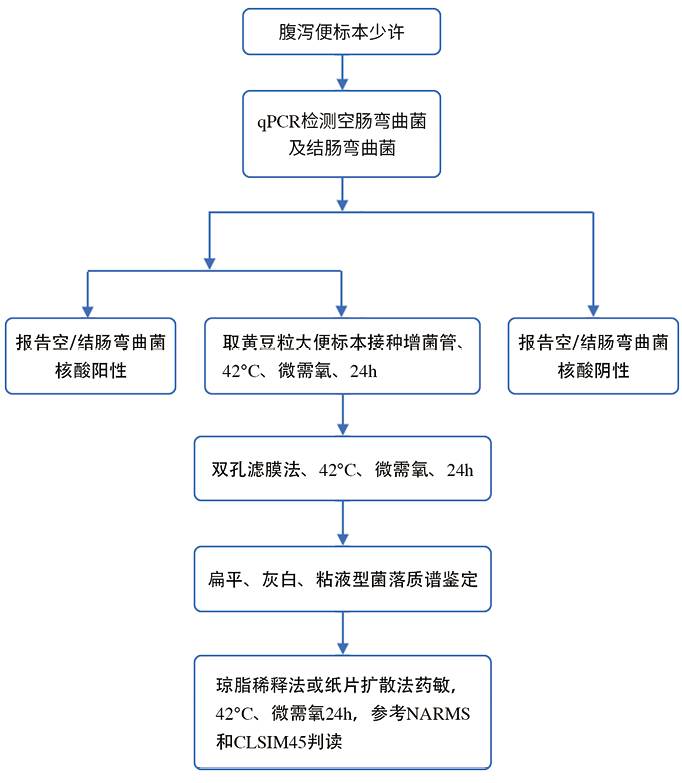

基于序列的分型方法,包括多位点序列分型 (MLST)、DNA微阵列和全基因组测序,提高了对弯曲菌流行株遗传进化及致病性的认识。MLST是基于七个高度保守的管家基因进行PCR扩增,对扩增片段进行测序,比较核苷酸序列,建立标准系统发育进化树的过程。MLST的优点是使用国际标准化的命名法,数据明确、高度可信并可复现。DNA微阵列法可 对弯曲菌的基因组进行分型,还可检测额外基因组元件、耐药性和毒力基因等,缺点是针对已知靶标和已知细菌,难以识别新发菌株,也无法区分基于MLST法的高度克隆株。下一代基因组测序(NGS)是研究毒力、耐药性和遗传进化更为强大的工具。通过全基因组NGS可发现基因组重排和重组,进一步分析物种进化特征,提高菌株追溯和环境监测的精确度。检验流程见图3。

注:qPCR:实时荧光定量聚合酶链反应;NARMS:美国国家肠道细菌耐药监测中心;CLSI:美国临床与实验室标准化学院

图3. 弯曲菌的实验室常规检验流程图

1. 培养方法:弯曲菌生长缓慢,有正常粪便菌群存在的情况下很难分离[60]。传统培养法是先将便标本进行增菌,然后转种于选择性培养基上,在42℃的微需氧环境中孵育48-72h[20]。临床常用的选择性培养基有:改良炭头孢哌酮脱氧胆酸盐琼脂(modified cefoperazone charcoal deoxycholate agar,mCCDA)、Campy-Line琼脂、Karmali琼脂、木炭选择性培养基(charcoal selective medium,CSM)和头孢哌酮,万古霉素,两性霉素B(Campy cefoperazone, vancomycin, amphotericin B,CVA)琼脂等[61-63]。培养基之间的主要区别是抑制杂菌的抗生素类型和浓度不同[54]。一项研究对4种选择性培养基进行性能评估,认为它们分离弯曲菌的效果相当,没有显著差异[64]。膜过滤培养法已证明可提高弯曲菌检出率,但是这种方法并没有得到广泛应用[65, 66]。虽然培养法是实验室主要选择,但由于存活但不可培养(VBNC)状态细菌的存在,以及肠杆菌科其他细菌的耐药性严重,弯曲菌极易被漏检,造成假阴性结果。本实验室数据证实,中国CDC监制的双孔滤膜法在临床上获得了较好的应用数据[50]。菌落鉴定简单快速的方法是MALDI-TOF质谱,基本解决了弯曲菌的鉴别问题。鉴定明确菌落可通过MH血平板置CO2培养箱48h进行AST(抗菌药物敏感试验),判断标准采用CLSI M45。KB纸片法的药敏结果对临床有良好的指导作用。